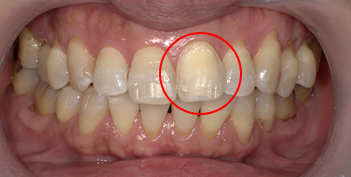

インターナルブリーチの治療例

インターナルブリーチとは、一般的に神経の死んでいる歯を専用の漂白剤を注入・洗浄することで白くする方法です。

- 30代 女性

| 年齢/性別 | 30代 女性 |

|---|---|

| 施術回数 | 3回 |

| 費用 | 5万5千円(税込) |